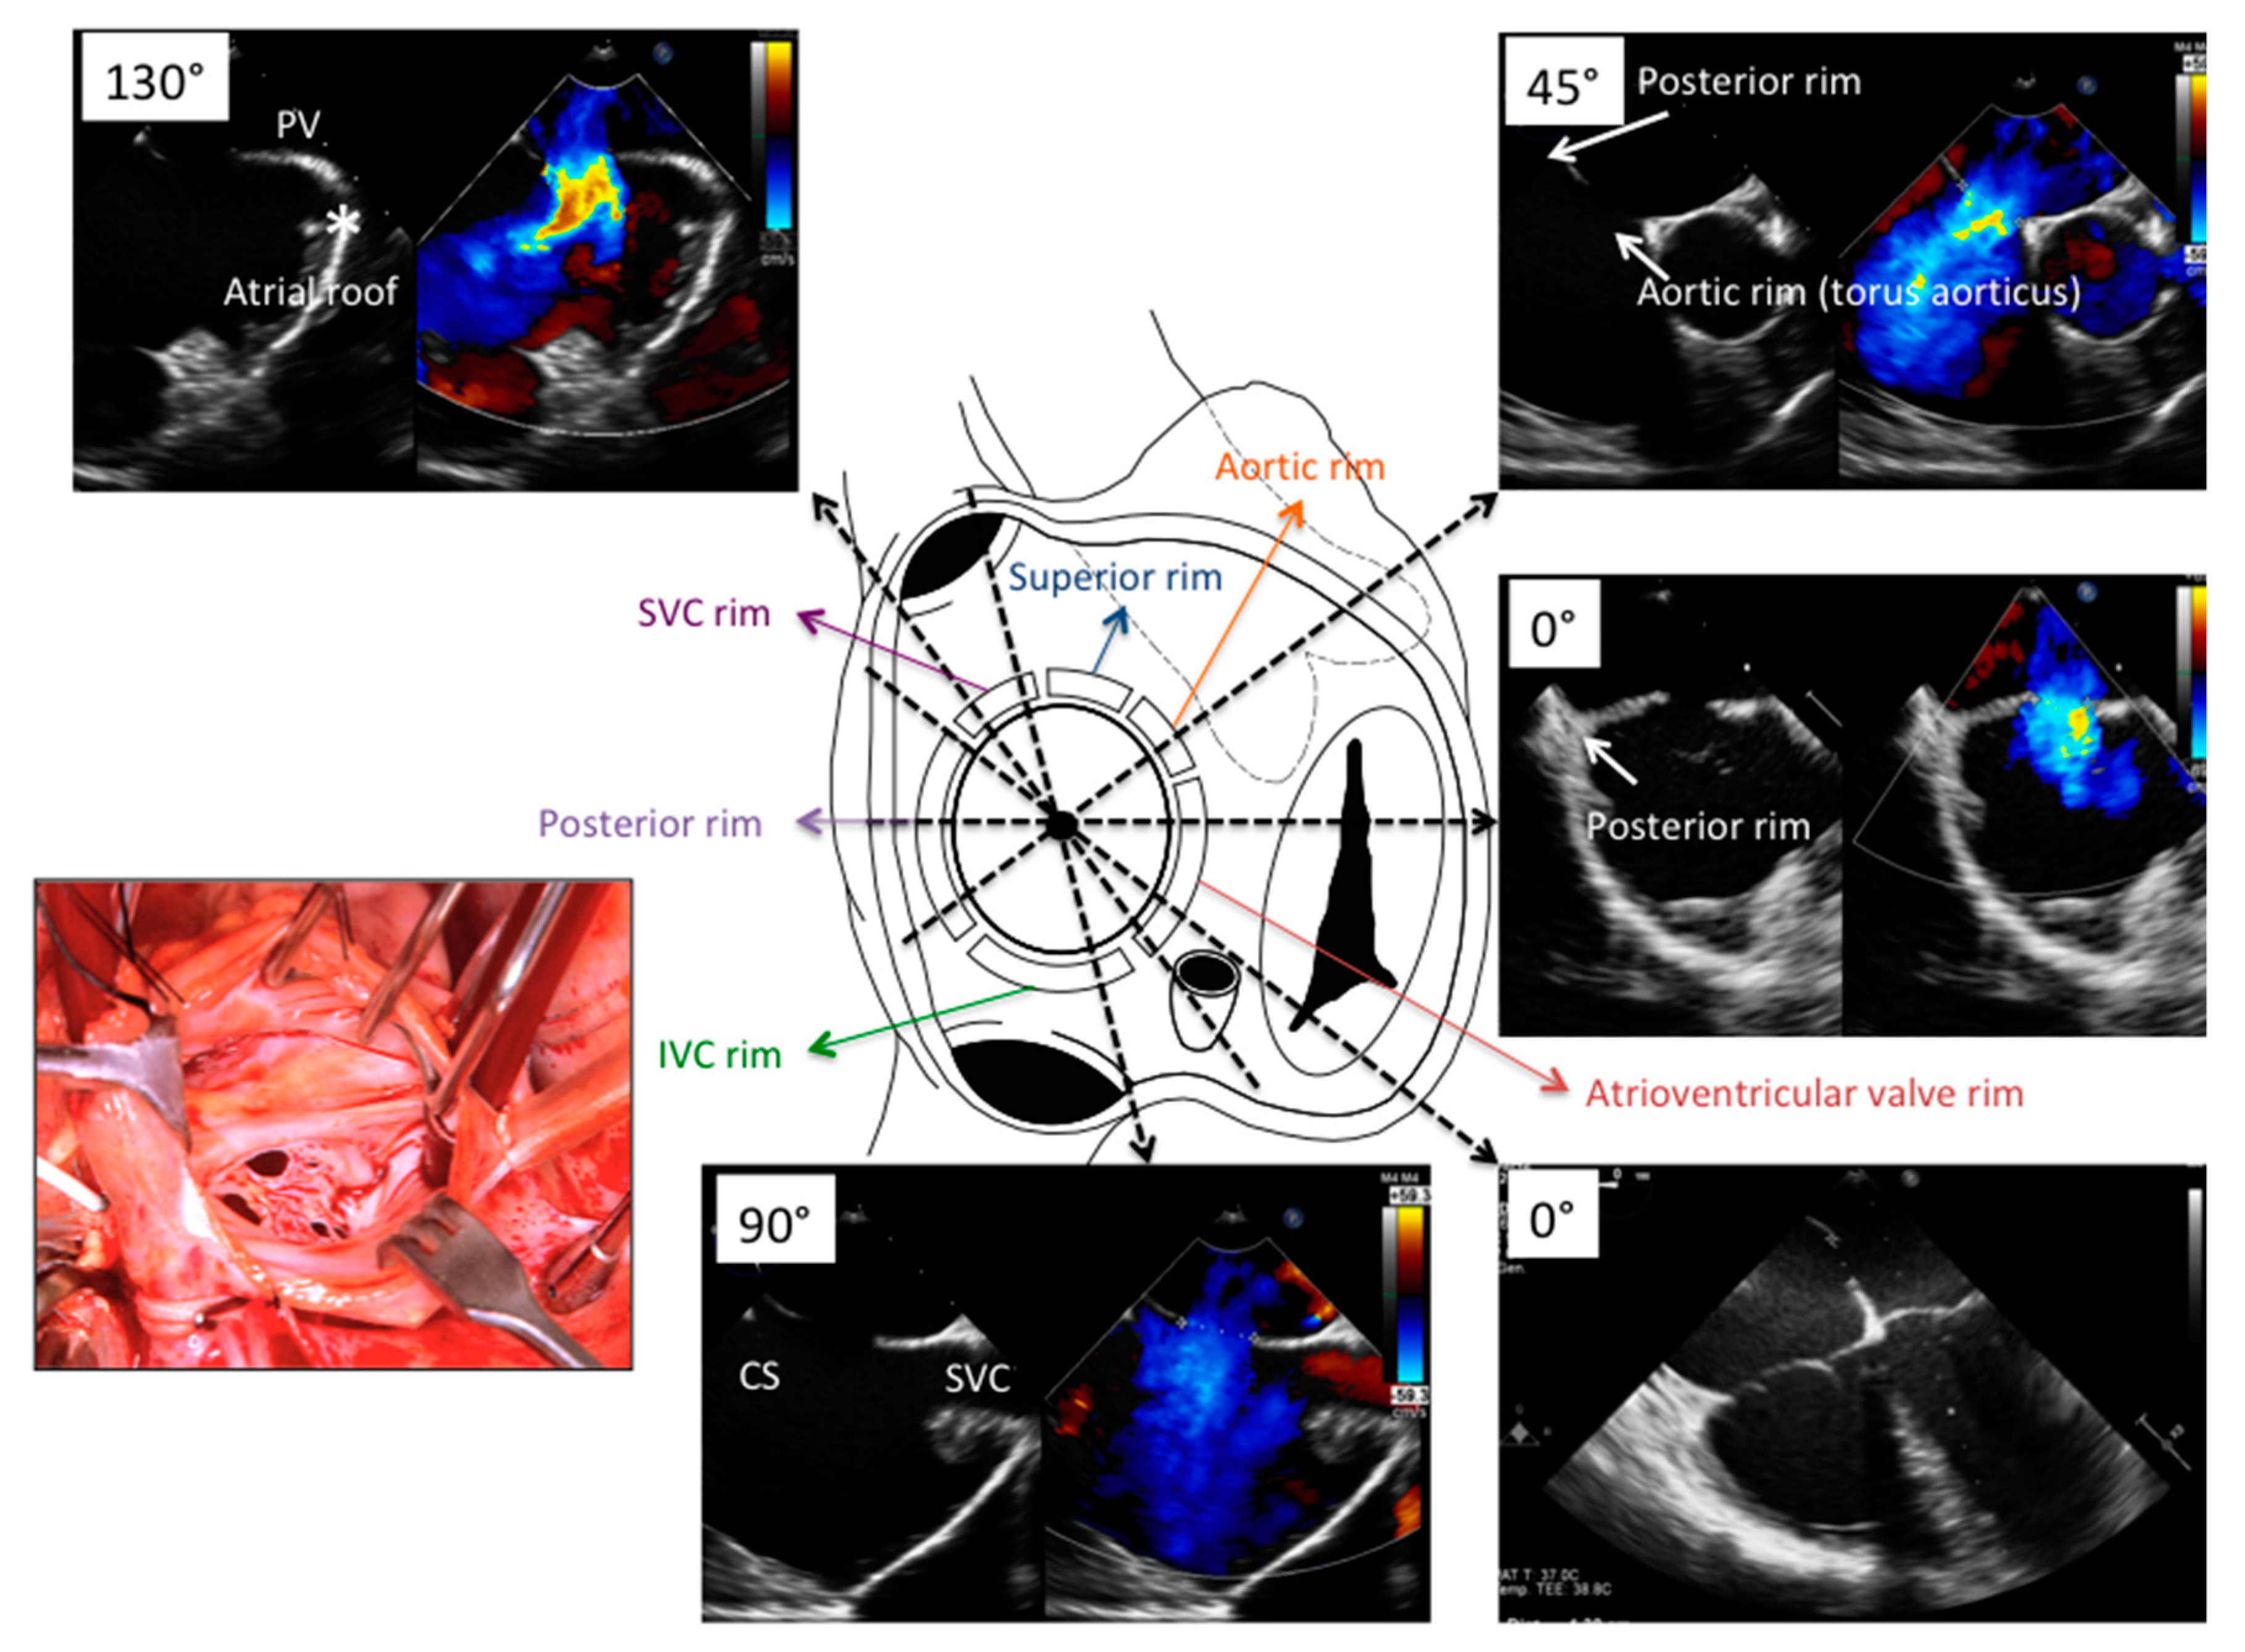

4. ASD

4.2. Perioperative Monitoring

| View | Atrial Septal Anatomy | Procedural Assessment | Suggested Multiplane Angles | Esophageal Position |

|---|---|---|---|---|

| Basal transverse | SVC, superior aortic, RUPV | Device relationship in atrial roof | 0°, 15°, 30°, 45° | Mid- to upper esophagus |

| Four-chamber | Posterior and AVV rims, maximal ASD diameter | Device relationship to AV valves | 0°, 15°, 30°, | Mid-esophagus |

| Short-axis | Posterior and aortic rims, maximal ASD diameter, PFO tunnel and atrial anterior-posterior distance | Device relationship to AoV and posterior atrial wall | 30°, 45°, 60°, 75° | Mid- to upper esophagus |

| Bicaval | IVC and SVC rims, maximal ASD diameter, PFO amplitude and lenght | Device relationship to RA roof/dome | 90°, 105°, 120° | Mid-to upper esophagus and deep transgastric |

| Long-axis | Dome/roof of LA | Device relationship to LA dome/roof | 120°, 135°, 150° | Mid- to upper esophagus |

| Before vascular access | Free LA appendage Normal aortic and mitral valve No intracardiac mass Atrial septal aneurysm Eustachian valve Chiari Network Accessory fenestration Antero-posterior septal distance | Free LA appendage No significant mitral valve disease Atrial septal aneurysm Eustachian valve Chiari Network Assess border features Multifenestrated ASD Confirm normal pulmonary vein anatomy Bidimensional and color-based shortest and largest ASD diameter 3D-based shortest and largest ASD diameter |

| After vascular access | Confirm right-to-left shunt at intracardiac bubble study Confirm correct tunnel wiring Confirm wire position in the proper pulmonary vein PFO tunnel amplitude and length | Confirm wire position in the proper pulmonary vein Balloon sizing in stop-flow condition |